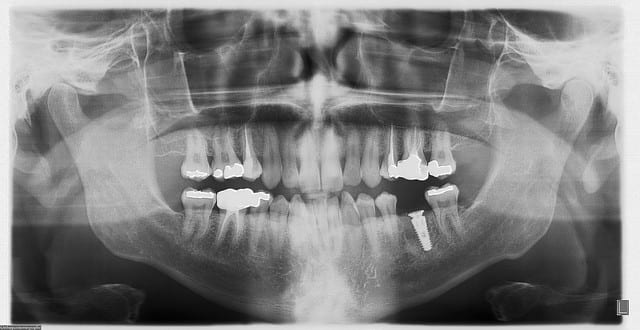

oh le cas clinique n'a rien de bien exceptionnel....une 36 à remplacer, par contre il est vrai avec une largeur de crête de folie (de mémoire je dois avoir 15mm!!!), une bonne douzaine de mm en prenant de la marge au dessus du NDI dans un os qui est cicatriciel (extraction il y a 5 ou 6 mois, je ne sais plus exactement) donc certainement D2 / D3, 10/11mm entre la 5 et la 7....bref: autoroute...

naturellement, un 5/11.5 va tranquillement y prendre place...;-)

@ fouilla: la vis de cicat n'est pas crestale, la pano est trompeuse, cette surélévation de 2mm va permettre d'augmenter la hauteur de tissu conjonctif dans cette zone.

il sera plus facile de "tricher" ensuite pour rendre l'émergence prothétique la plus anatomique possible...